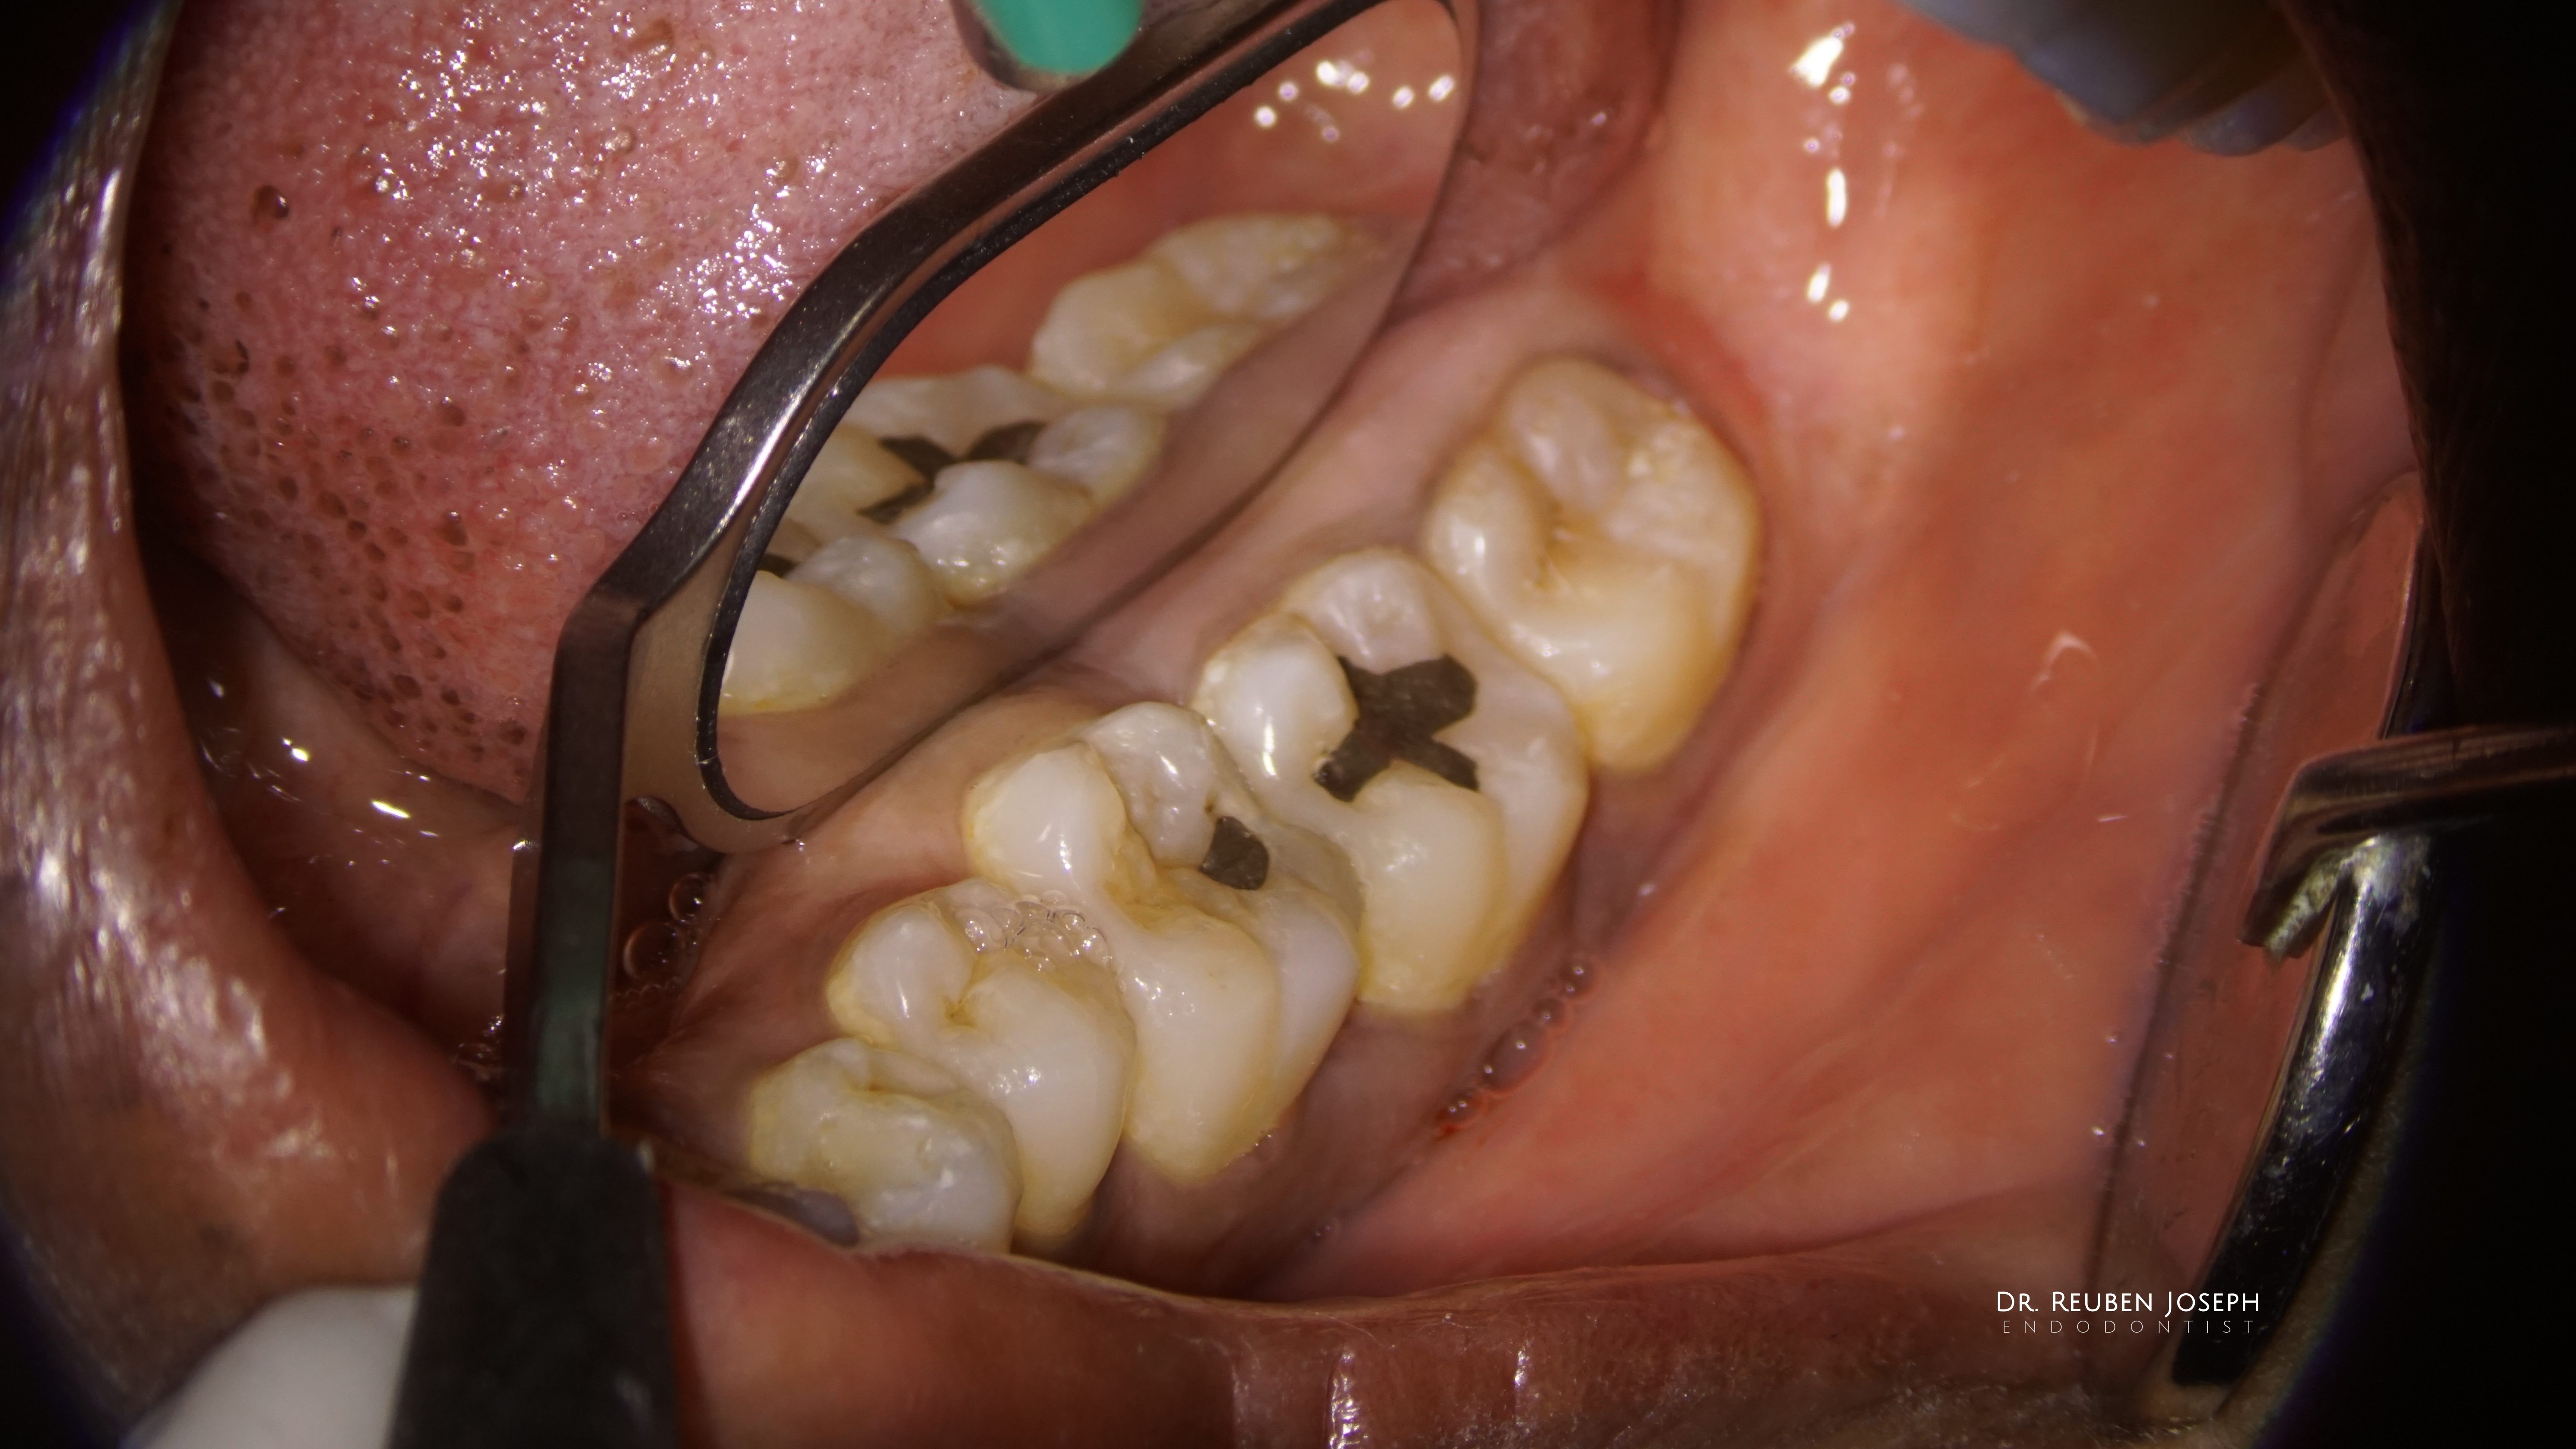

#18 RCT

With this kind of gingiva sinking the whole tooth an indirect post-endo would have been a nightmare (atleast for me) in this case. Orifice directed access done and the carious lesion prepared and restored separately along with the DO in the 19, the cuspal integrity is intact so just the direct composite post the endo.